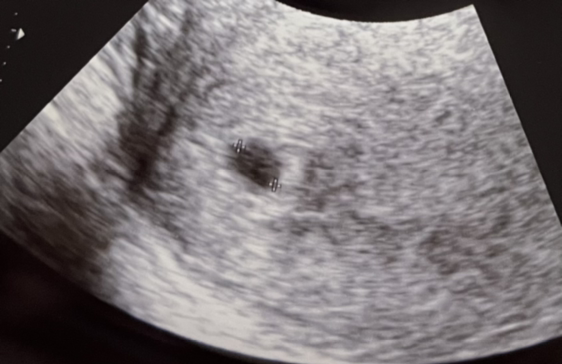

아기집이 생겼다. 아내의 초음파 사진에 아주 작은 주머니가 하나 찍혔다.

0.62cm짜리 집이란다. 이제 저 작은 집에서 파이리가 자라날 거다. 파이리의 크기가 얼마나 될지는 모르겠지만, 집이 작아 보인다. 파이리가 0.1cm만 돼도 집 크기가 몸 크기의 6배밖에 되지 않는다.